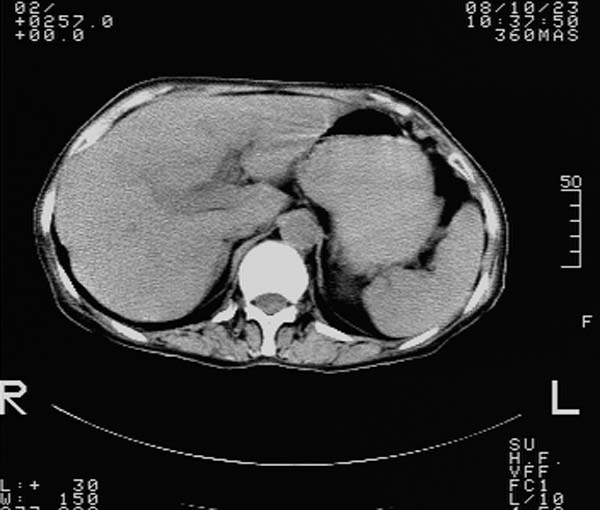

f,67y。反复右上腹痛。余无异常。

前五幅未服造影剂。后面图像有上传重复的。请战友们发表意见。

胆囊结石、胆囊癌伴邻近脏器受侵,不除外黄色肉芽肿性胆囊炎,建议增强扫描。肝多发囊性占位性病变,囊肿或囊性转移。

胆囊内结石,胆囊壁不规则增厚,胆囊胃窦区解剖结构欠清晰,楼主提示为少见病,考虑bouveret综合征?黄色肉芽肿性胆囊炎?肝内多发低密度占位,建议增强或b超